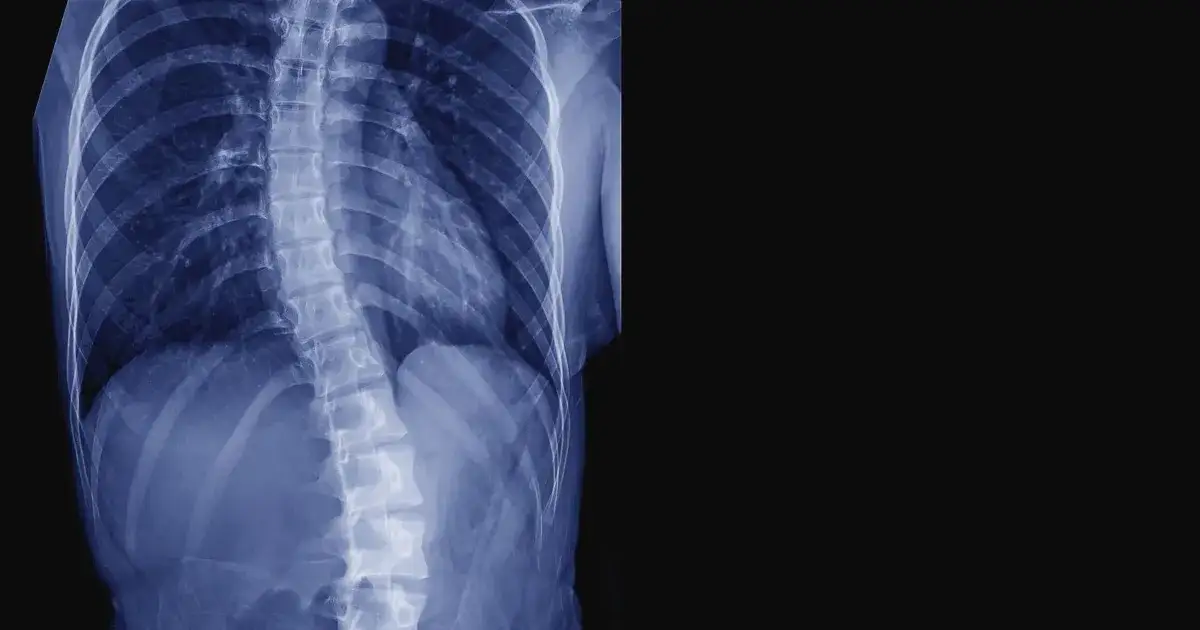

Objawy skoliozy lewostronnej są często zauważalne i mogą być kluczowe w wczesnym rozpoznaniu tej choroby. Wśród głównych symptomów znajdują się widoczne wygięcie kręgosłupa na lewą stronę oraz asymetria w wysokości bioder, co może prowadzić do dalszych problemów zdrowotnych. Zrozumienie tych objawów jest istotne, aby podjąć odpowiednie kroki diagnostyczne i terapeutyczne na czas.

Inne ważne oznaki to nierówna pozycja stojąca oraz asymetria talii, które mogą wpływać na komfort codziennego życia. W przypadku skoliozy lewostronnej piersiowej, mogą występować dodatkowe zmiany, takie jak spłaszczenie kifozy czy rotacja kręgów. Wczesne zauważenie tych symptomów może pomóc w uniknięciu poważniejszych powikłań w przyszłości.

Innym istotnym symptomem jest widoczne skrzywienie kręgosłupa podczas pochylania się do przodu. Osoby z lewostronnym skrzywieniem mogą zauważyć, że ich ciało nie jest w pełni symetryczne, co może prowadzić do dyskomfortu i bólu. Obserwacja tych symptomów jest kluczowa, aby zrozumieć, jak skolioza wpływa na postawę i ogólny stan zdrowia.

W diagnostyce skoliozy lewostronnej wykorzystuje się różne badania obrazowe, które pozwalają na dokładną ocenę stanu kręgosłupa. Najczęściej stosowaną metodą jest rentgen, który umożliwia uzyskanie szczegółowych zdjęć kręgosłupa w różnych płaszczyznach. Dzięki temu lekarz może ocenić kąt skrzywienia oraz jego wpływ na inne struktury ciała. Inną popularną metodą jest rezonans magnetyczny (MRI), który dostarcza jeszcze dokładniejszych informacji o tkankach miękkich oraz narządach wewnętrznych. Obie te metody są niezbędne do postawienia trafnej diagnozy i zaplanowania dalszego leczenia.